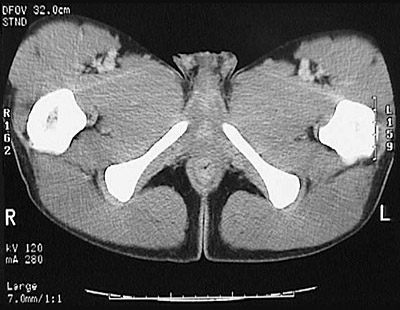

[Upper Femur] This is a normal pelvic CT scan in a male demonstrating the right pubic ramus and left pubic ramus and right femur and left femur and anal canal and gluteal fold and gluteus maximus in the lower pelvis.